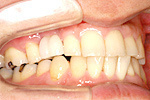

症例 14

① 前歯1本が無い状態です。通常は前後の2本の歯を削ってブリッジにしますが、インプラントをすることにより、健康な歯を削る必要はなくなります。

② インプラントが埋め込まれて安定した状態です。

③ インプラントに固定式の歯が入ったところです。健康な自分の歯を守る事ができました。

20才代 女性

総額:42万円(税別)

リスク副作用:顎骨の変化により、自分の歯との間に隙間や段差が生じることがあります。